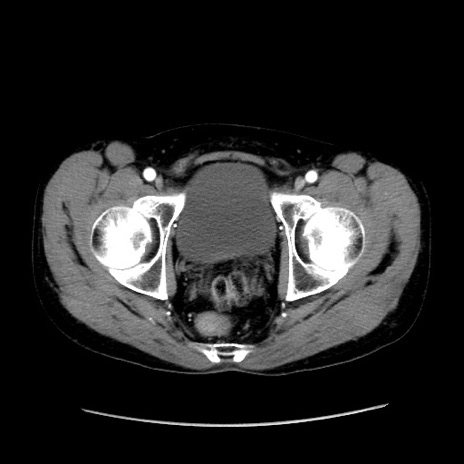

冠状断像

【症例】40歳代 男性

【主訴】腹痛

【現病歴】4時間ほど前に電車に乗車中に臍部上より腹痛出現。徐々に増悪し起立困難となり、救急外来受診。生ものは数日食べていない。今朝お雑煮を食べた。

【身体所見】BT 36.8℃、BP 117/84mmHg、HR 91/min、SpO2 97%、苦悶様、腹部:臍上部広範囲圧痛あり、反跳痛±

【データ】WBC 8100、CRP 0.03